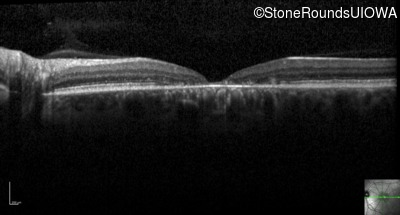

Optical Coherence Tomography - Left - 20/160 +2

Exemplar / OCT Stack

OCT Stack